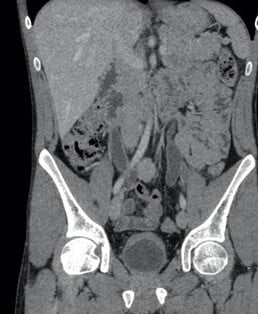

A contrast CT reveals bladder and ureteric wall thickening accompanied by hydroureteronephrosis. Ketamine usage can induce a painful, contracted, and fibrotic bladder, consequently reducing compliance, escalating end-fill pressures, and, in certain cases, resulting in hydronephrosis. Monitoring includes the patient’s airway, breathing, and circulation, as ketamine can potentially cause cardiopulmonary compromise, especially when taken in combination with other drugs. Patients who have recently ingested PCP orally may benefit from gastrointestinal decontamination. Activated charcoal is effective in adsorbing PCP and enhancing its nonrenal clearance. However, due to the potential for rapid changes in mental status, the use of ipecac syrup and GI lavage is not recommended for decontamination. Activated charcoal is typically given in a dose of 1 g/kg, with a maximum oral dose of 50 g. However, activated charcoal should be avoided in patients with unprotected airways or absent bowel sounds. Administration of activated charcoal within a sufficiently brief amount of time may prevent the need for gastric lavage. Hemoperfusion and dialysis tend to be ineffective due to ketamine’s large volume of distribution.